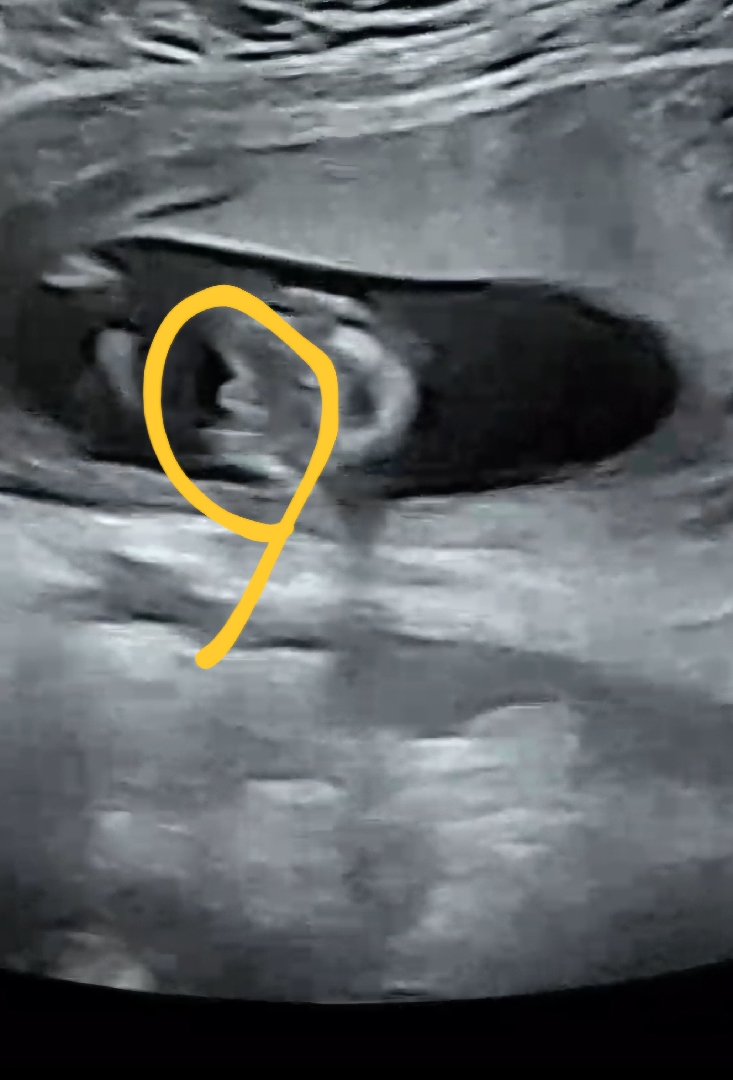

13주3일 성별 보이시나요?!!

오늘 교수님이 다리사이에 뭐가 보이는거 같은데 무슨말인지 알죠? 하시구서 그래도 담에 봐야 정확하다 하셨는데용!